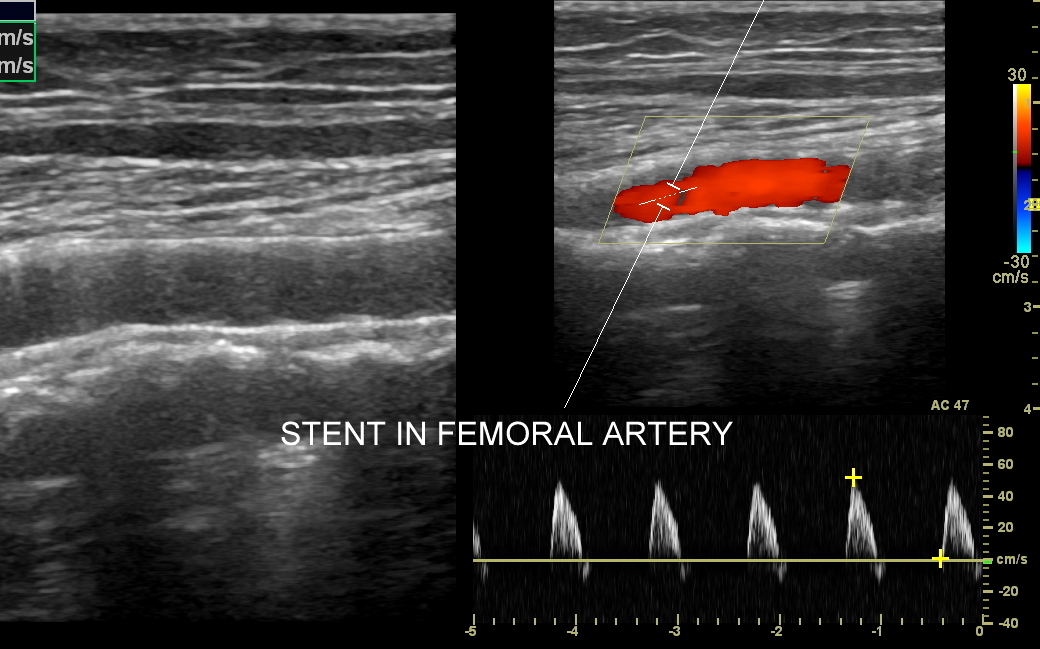

Badanie USG Doppler tętnic, klasyczne badanie angiograficzne oraz badanie angio-TK to podstawowe i uzupełniające się metody diagnostyczne naczyń. Badanie dopplerowskie w przeciwieństwie do dwóch pozostałych jest metodą oceny funkcjonalnej a nie tylko wizualnej, tzn. oprócz stopnia zwężenia tętnicy ocenia również zaburzenia przepływu w oraz za zwężeniem, a także zaburzenia ukrwienia dystalnego tkanek.

Badanie USG Doppler tętnic kończyn dolnych wykonywane jest najczęściej w ramach diagnostyki miażdżycy zarostowej tętnic kończyn i jej objawów w postaci chromania przestankowego, czyli bolesności łydek, rzadziej ud i pośladków, pojawiających się w trakcie wysiłku fizycznego. Inne wskazania do USG tętnic kończyn dolnych obejmują uczucie chłodnych stóp, marznięcie nóg, diagnostykę zespołu zespół  Raynauda, czy choroby Buergera. W stanach nagłych badanie wykonuje się w przypadku ostrego niedokrwienia np. na tle obwodowej zatorowości tętniczej. Rzadsze patologie, które pojawiają się w obrębie tętnic kończyn dolnych to tętniaki prawdziwe, tętniaki rzekome (pseudotętniaki) i rozwarstwienia. Tętniaki rzekome są zwykle efektem powikłań jatrogennych nakłuć, a rozwarstwienia wynikiem urazów tętnicy, np. podczas uprawiania sportu.

Podczas wykonywania USG Doppler kończyn dolnych bada się osie tętnicze obu kończyn, które obejmują takie tętnice jak tętnica udowa wspólna, powierzchowna, głęboka, podkolanowa, tętnica piszczelowa przednia, tylna i tętnica strzałkowa. Ocenia się również ewentualne zwężenia oraz tzw. krążenie oboczne; poszukuje się cech zatorowości, zapalenia, rozwarstwienia i cech tętniaków.